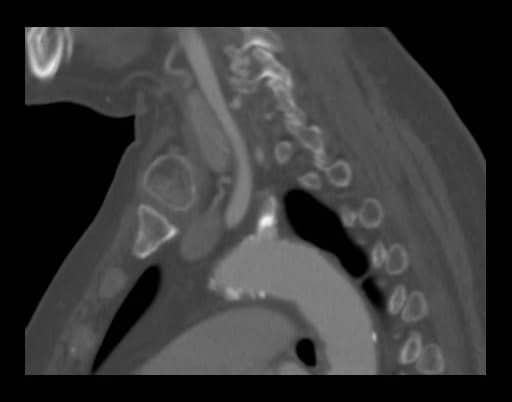

図2.造影CT早期動脈相矢状断

左鎖骨下動脈起始部は石灰化により高度狭窄が疑われた。